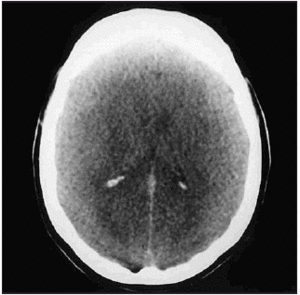

Se trataba de una mujer de 17 años, sin antecedentes médicos de interés, que acudió a una fiesta donde consumió un comprimido y medio de éxtasis e importantes cantidades de agua. Pocas horas después fue trasladada por un familiar a nuestro hospital por presentar, de manera brusca, deterioro del nivel de conciencia, con importante agitación psicomotriz, sin conexión con el medio, ni respuesta a órdenes verbales. Fue valorada inicialmente por el servicio de urgencias, donde llegó con una puntuación en la escala de Glasgow (GCS) de 6: O1+M4+V1. Estaba agitada y sin respuesta a órdenes. Las pupilas eran isocóricas, débilmente reactivas, sin apertura ocular espontánea ni ante estímulos nociceptivos. Presentaba movimientos de retirada en extremidades superiores. Durante su estancia en urgencias progresó el deterioro del nivel de conciencia, por lo que se procedió a intubación orotraqueal y conexión a ventilación mecánica. Se realizó una tomografía axial computarizada (TAC) craneal sin observarse signos de edema cerebral, ni desviación de la línea media, ni lesiones ocupantes de espacio. En la analítica de urgencias destacaba la presencia de sodio en sangre de 119 mEq/l, que se confirmó en una nueva determinación, una osmolaridad plasmática de 240 mOsm/kg, un sodio en orina de 183 mEq/l y una osmolaridad en orina de 685 mOsm/kg, con creatinfosfocinasa (CPK) en plasma de 2.082 U/l. La determinación de tóxicos en orina fue positiva para derivados anfetamínicos. La paciente ingresó en nuestro servicio, y se inició la corrección lenta del déficit de sodio y restricción de líquidos. A los 30 min del ingreso presentó un deterioro agudo neurológico con midriasis bilateral arreactiva y movimientos de descerebración espontáneos en las 4 extremidades. Se realizó una nueva TAC craneal urgente en la que se objetivó la existencia de edema cerebral difuso y masivo, con borramiento de cisternas (fig. 1). Se decidió controlar la presión intracraneal con un catéter intraparenquimatoso de presión intracraneal (PIC), con una primera medida mayor de 60 mmHg. Se inició tratamiento antiedema, con suero salino hipertónico y bolos de manitol, sin obtener descenso de la PIC ni respuesta clínica. Dos horas más tarde la exploración clínica era compatible con muerte cerebral, lo que se confirmó con diversas exploraciones complementarias: electroencefalograma (EEG), potenciales evocados y Doppler transcraneal (DTC) (fig. 2). Tras el fallecimiento de la paciente se practicó la autopsia y los datos toxicológicos postmortem confirmaron la presencia de MDMA en diversas muestras de sangre (0,03 mg/ml), cavidad gástrica (14,54 mg/g), orina (0,23 mg/ml) y humor vítreo (0,02 mg/ml).

Figura 1. Tomografía axial computarizada craneal: edema cerebral masivo.